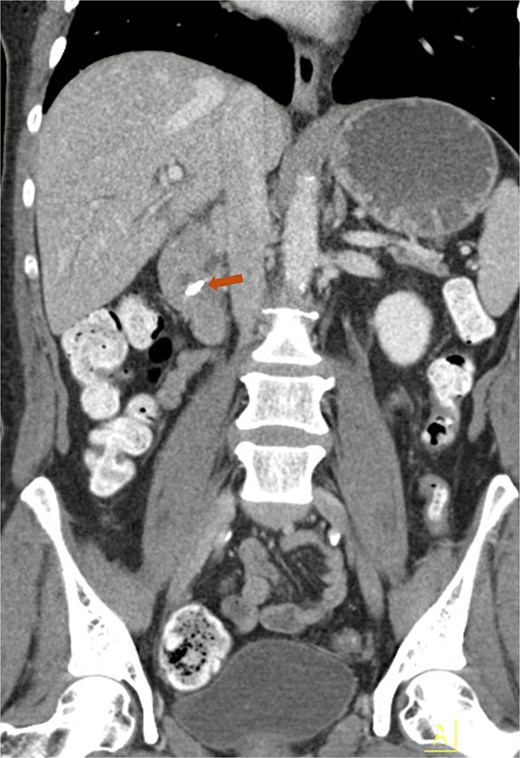

Contrast-enhanced abdominal computed tomography (CT) scan revealed a surgically absent gallbladder. A surgical clip was identified in the region of the ampulla of Vater, and a 4 mm stone was located in the distal common bile duct just proximal to the ampulla (Fig. 1). Subsequently, ERCP was performed, during which a 6 mm brown pigment stone was identified in the middle third of the main bile duct. In addition, a metallic foreign object resembling a surgical clip was noted within the stone (Fig. 2). Biliary sphincterotomy was performed using a traction sphincterotome and electrocautery. The biliary tree was then swept with a 15 mm balloon starting at the bifurcation, and the sludge was removed from the duct. The stone was successfully retrieved using Roth Net (Fig. 3), and a plastic stent was placed in the ventral pancreatic duct. The patient’s liver function test results improved following the procedure, and the patient was discharged. Passage of the pancreatic duct stent was confirmed by abdominal radiography.

Contrast-enhanced CT of the abdomen demonstrating a migrated clip in the common bile duct (arrow).